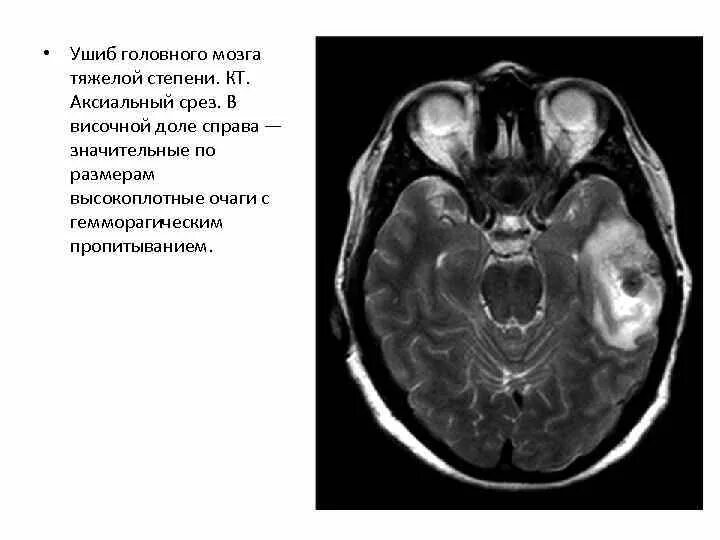

Ушиб мозга на кт